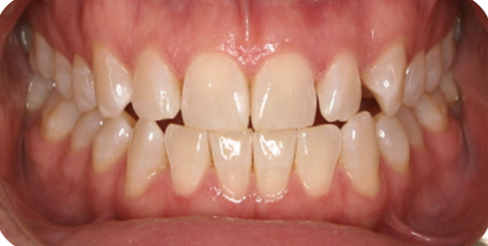

adult invisalign

Before

After